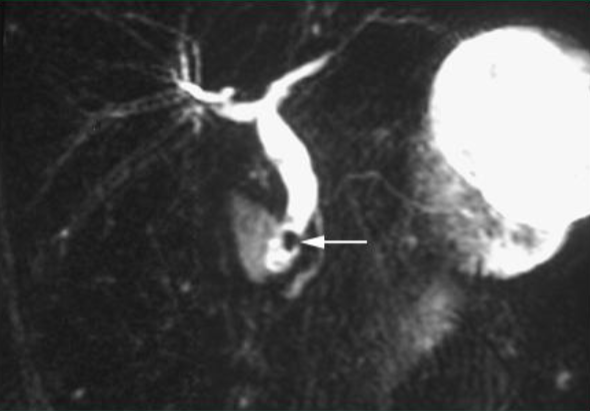

Magnetic Resonance Cholangiopancreatography (MRCP)

Noninvasive

Alternative if US negative

Common bile duct stone

MRCP

Endoscopic US

MRCP or endoscopic US can be done first for dx, only doing ERCP if needed for stone removal